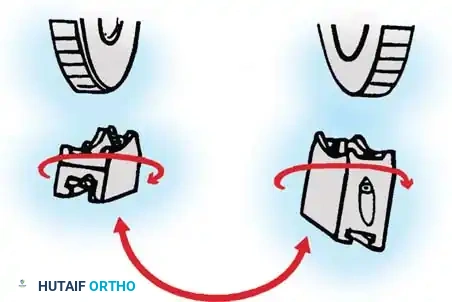

To convert it for a left arm, remove the proximal 5/8-inch ring by loosening the T-bolts. Remove the proximal blocks using a 9/64-inch hex wrench.

Fig. 58-28B Switch the blocks to the opposite wheel, rotating each block 180 degrees so the tilt is reversed.

Resecure the blocks tightly and replace the proximal ring.